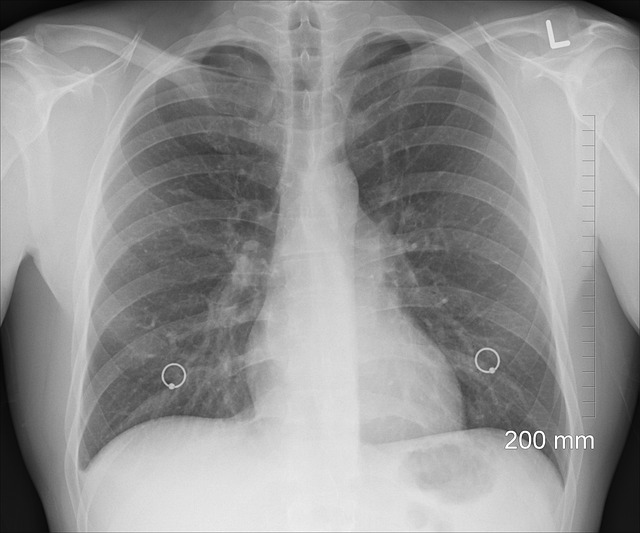

- 흉부 X-ray: 마이코플라즈마 폐렴의 경우, X-ray 상에서 특유의 패턴을 확인할 수 있습니다. 그러나 마이코플라즈마 폐렴은 다른 폐렴과 달리 비교적 덜 심한 폐렴 형태를 보일 수 있어, 영상에서 큰 변화가 없을 수도 있습니다.